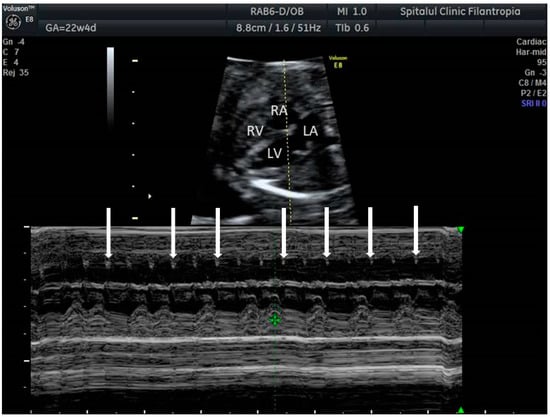

2. The Use of Ultrasound to Assess Fetal Heart Rhythm

5.4. Heart Block